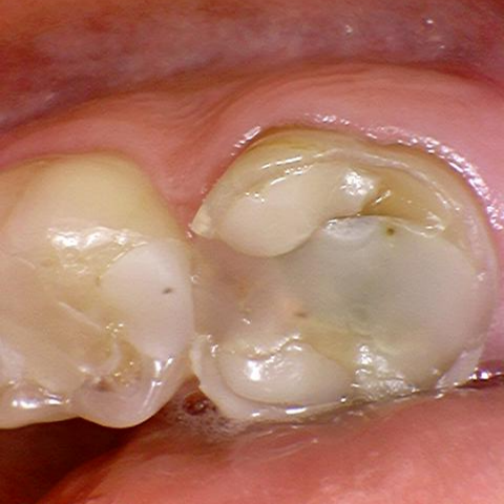

HOIDOT PURENTAVAIVOIHIN

On paljon hammasvaivoja, joihin on olemassa helppojakin hoitoja. Asiantuntevalta hammaslääkäriltä saat hammastarkastuksessa analyysin oman suusi terveydestä. Tässä kuvassa potilaan vaivana oli purressa lohkeavat hampaat. Kyseessä oli kuluneiden hampaiden väärään asentoon ohjaama (eli ristipurentaan) purenta ja sen myötä syntyneet lisävauriot, kulumat ja lohkeamat. Nämäkin hampaat hoidettiin kuntoon, suun terveys palautui ja ilmeestä tuli entistä ehompi, raikas ja hurmaava. Lue koko purentahoidon eteneminen tästä ja katso hämmästyttävät kuvat ennen ja jälkeen.

purentavirhe, ristipurenta